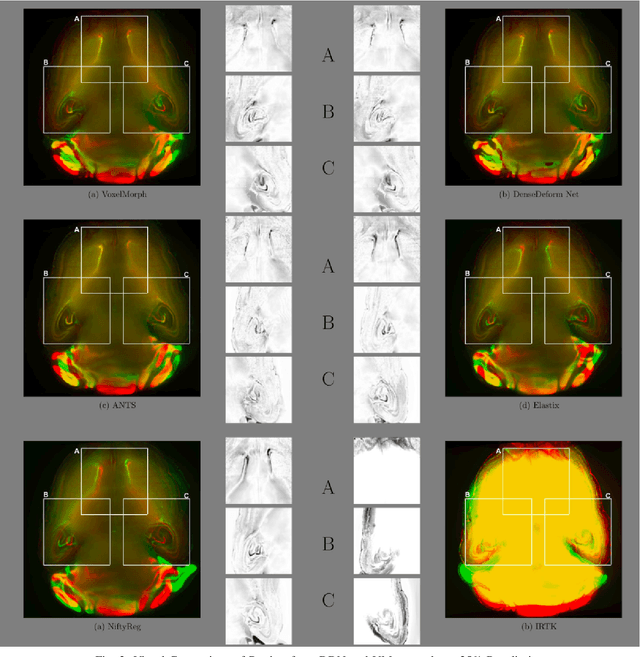

Abstract:The recent application of Deep Learning in various areas of medical image analysis has brought excellent performance gain. The application of deep learning technologies in medical image registration successfully outperformed traditional optimization based registration algorithms both in registration time and accuracy. In this paper, we present a densely connected convolutional architecture for deformable image registration. The training of the network is unsupervised and does not require ground-truth deformation or any synthetic deformation as a label. The proposed architecture is trained and tested on two different version of tissue cleared data, 10\% and 25\% resolution of high resolution dataset respectively and demonstrated comparable registration performance with the state-of-the-art ANTS registration method. The proposed method is also compared with the deep-learning based Voxelmorph registration method. Due to the memory limitation, original voxelmorph can work at most 15\% resolution of Tissue cleared data. For rigorous experimental comparison we developed a patch-based version of Voxelmorph network, and trained it on 10\% and 25\% resolution. In both resolution, proposed DenseDeformation network outperformed Voxelmorph in registration accuracy.

Abstract:Image registration plays an important role in comparing images. It is particularly important in analyzing medical images like CT, MRI, PET, etc. to quantify different biological samples, to monitor disease progression and to fuse different modalities to support better diagnosis. The recent emergence of tissue clearing protocols enable us to take images at cellular level resolution. Image registration tools developed for other modalities are currently unable to manage images of such extreme high resolution. The recent popularity of deep learning based methods in the computer vision community justifies a rigorous investigation of deep-learning based methods on tissue cleared images along with their traditional counterparts. In this paper, we investigate and compare the performance of a deep learning based registration method with traditional optimization based methods on samples from tissue-clearing methods. From the comparative results it is found that a deep-learning based method outperforms all traditional registration tools in terms of registration time and has achieved promising registration accuracy.

Abstract:Recent progress in tissue clearing has allowed for the imaging of entire organs at single-cell resolution. These methods produce very large 3D images (several gigabytes for a whole mouse brain). A necessary step in analysing these images is registration across samples. Existing methods of registration were developed for lower resolution image modalities (e.g. MRI) and it is unclear whether their performance and accuracy is satisfactory at this larger scale. In this study, we used data from different mouse brains cleared with the CUBIC protocol to evaluate five freely available image registration tools. We used several performance metrics to assess accuracy, and completion time as a measure of efficiency. The results of this evaluation suggest that the ANTS registration tool provides the best registration accuracy while Elastix has the highest computational efficiency among the methods with an acceptable accuracy. The results also highlight the need to develop new registration methods optimised for these high-resolution 3D images.